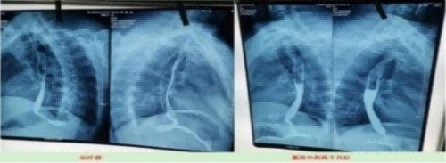

这是治疗前:病变长约7㎝。从吃饭困难到滴水不进。

2023年10月9日在山西肿瘤检查:病变长度7㎝。从2023年10月28月开始服用中药;2024年3月24日拿中药:2024年8月29日山西肿瘤医院复查(病变7cm癌变消失)。

目前:吃饭一大碗,一切很好,参加农业劳动。这是一位贫困山村的农妇。

上图是服用两个月中药的前后对比图

上图是服用两个月中药后检查报告对比图